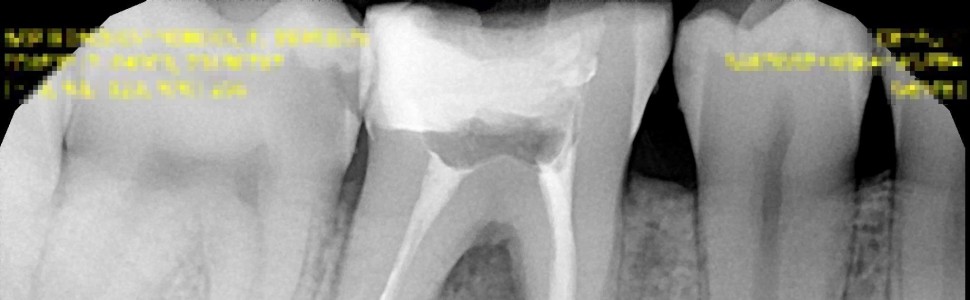

W pracy przedstawiono leczenie zęba 46 z przewlekłym ropnym zapaleniem tkanek okołowierzchołkowych obejmującym bifurkację. Efekty przeprowadzonej terapii badano klinicznie i radiologicznie przez 12 miesięcy.

The study describe a root canal treatment with chronic purulent periapical inflammation including bifurcation. The results of the therapy were clinically and radiologically examined over a 12-month period.